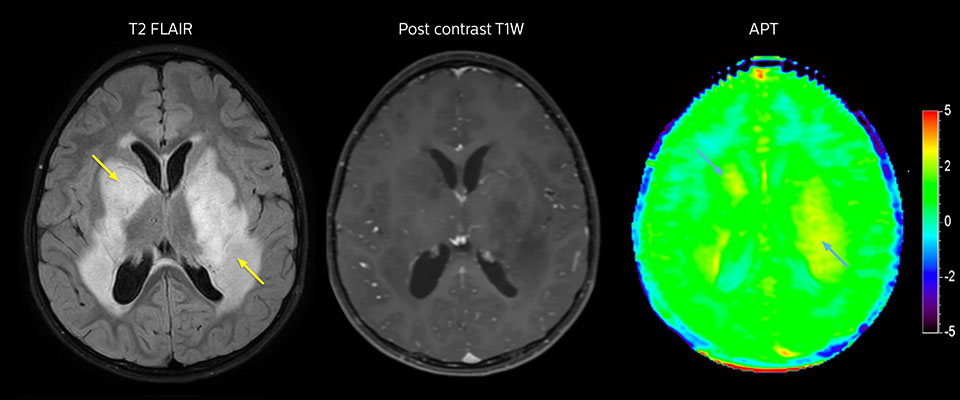

Low-grade glioma in a 5-year-old patient with neurofibromatosis 1. This low-grade lesion does not enhance on the post-contrast images, but does show an intermediate APT signal. The lesion stability over time confirms that it is a low-grade pathology.

Dr. Jeffrey Miller, pediatric radiologist at PCH also noticed the relation between APT contrast and tumor grades in the studies done at his hospital. “In several cases we have seen a high APT signal in high-grade tumors and moderately increased APT signal in cases with intermediate and low-grade tumors that have the characteristic of high signal change on T2 and FLAIR, and no contrast enhancement.” He points out the potential clinical implications of this observation. “When we’re faced with patients where the diagnosis is a little bit ambiguous, we often have to make choices and value judgements, which could mean either just following up the tumor or lesion, with the risk that it could change when we were wrong and there could be time lost. Or we have to go into invasive situations where we have to biopsy.” “It would be very impactful and valuable to have a sequence like APT weighted imaging, which could assist us in making those decisions with more confidence. That would be meaningful for the individual patients and take out some ambiguity in what we are doing.” “However, in order to reach that lofty goal, we will need more investigation, use the sequence in a larger population, and gain more understanding of situations and conditions where APT has its maximal value.”